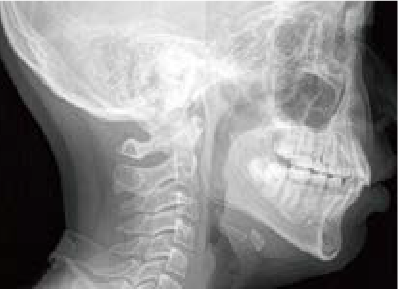

鼻がつまりやすく、口呼吸をしているために上あごが狭い状態でした。また上の前歯がかなり前へ傾いているため、お口をきちんと閉じていることができません。さらに、下の前歯もでこぼこしていました。

治療を終えて

装置によって上あごを拡大し、下あごを少し前へ成長させたことで、永久歯がきれいに並ぶスペースを確保しました。また、お口の機能が向上したことから鼻がよく通るようになり、口呼吸も改善され口も閉じやすくなったので顔の表情もよくなりました。

主訴・治療内容 下あごが後ろに下がり、出っ歯のようになっていることを心配して、無料相談に来院されました。

治療期間 2年半

費用 462,000円(税込)